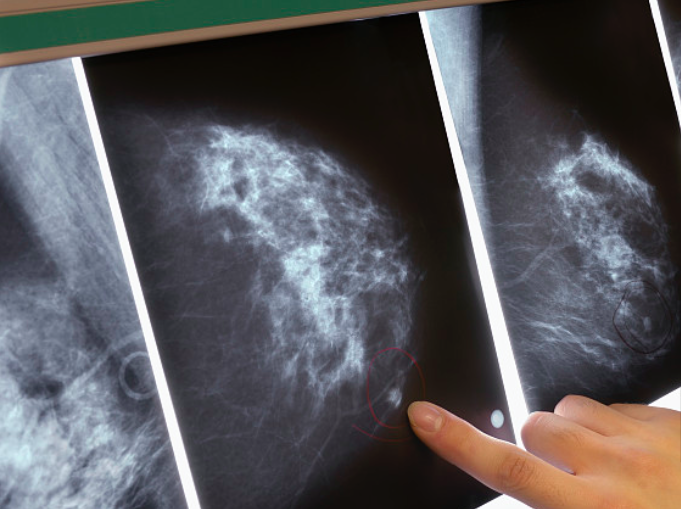

图片来源于视觉中国,与本文无关